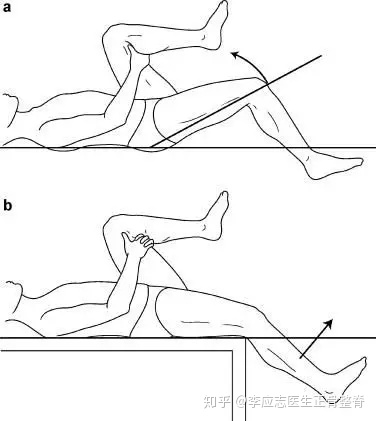

您的临床检查可能包括以下骨科检查,用于确定SI关节是否受累。

在这种姿势下,SI关节的问题会因为关节的压力而引起疼痛。

⑧骨盆分离、挤压试验阳性,骶髂关节“4”字试验阳性,下肢后伸试验阳性,单足站立试验阳性。